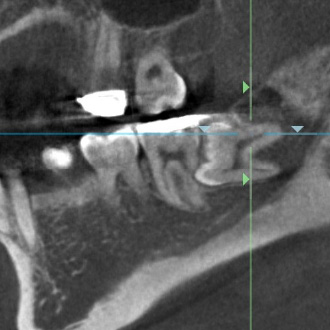

CT スキャンなどを活用して、歯と噛み合わせなどの総合的な検査をします。

治療が難しくトラブルが多い「根」の病気は、CT 撮影し、先進の根管充填材で治療するため安心です。

CT スキャンを用いて 3 次元的に確認をして、トラブルの少ない治療を行います。